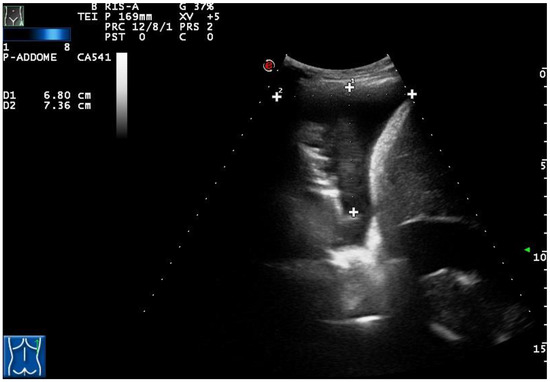

Figure 3. A complex nonseptated pleural exudate in a patient with pneumonia, measured by two orthogonal views (longitudinal and transversal), viewed by longitudinal scan using a convex multifrequency probe (3.5 MHz).